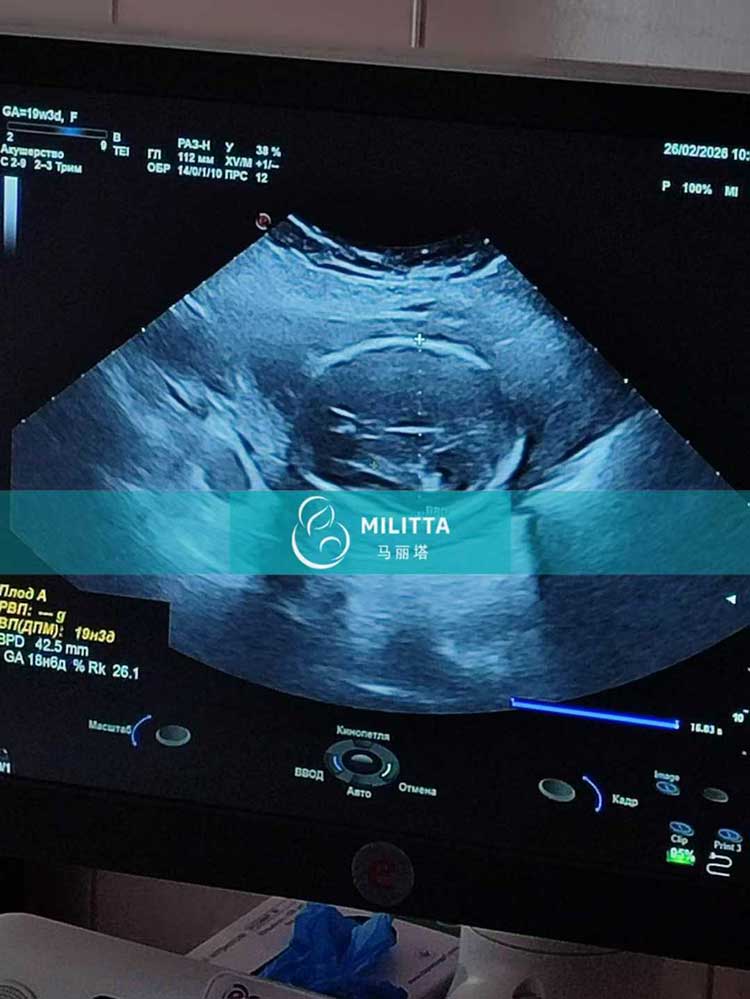

温女士夫妇到乌克兰匹配的孕妈完成孕19周B超检查

温女士夫妇到乌克兰匹配的孕妈完成孕19周B超检查,宝宝发育情况很好,一切平安顺利,辛苦孕妈一路的付出与坚持❤️